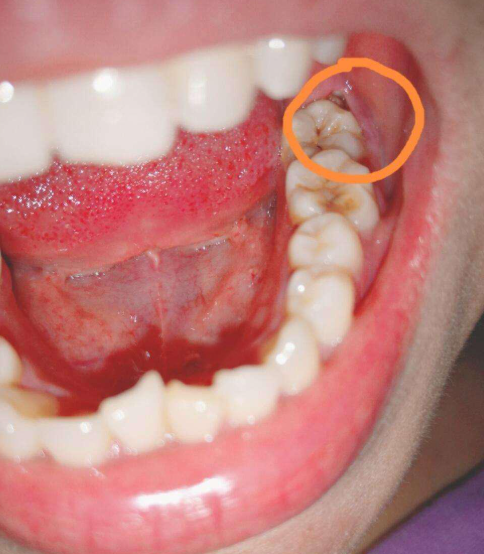

大牙外侧又长了个牙齿,这种情况最常见的原因是智齿或多生牙